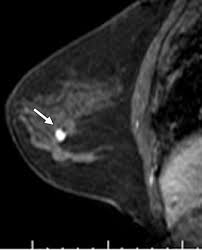

- On MRI, IDP (L/C ST) appears as dilated ducts with an associated enhancing, well-circumscribed mass:

- MRI is currently the most sensitive imaging modality for detecting IDP (L/C ST).